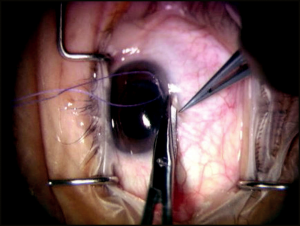

Scleral Flap Closure

The scleral flap should be closed tightly enough to prevent postoperative hypotony. The flap is closed with interrupted 10-0 nylon sutures. A 3-1-1 knot buries well and secures the flap adequately. Usually 3 to 5 sutures are used to adequately close the flap (Figure 4-8). After the flap is secured, the anterior chamber is reformed through the paracentesis with balanced salt solution, and the filtration is checked at the flap mar-gins with a Weck-Cel sponge. If the IOP and anterior chamber depth are maintained with slow oozing of aqueous humor, then the scleral flap clo-sure is usually adequate. However, if aqueous humor flows freely and the anterior chamber shallows, additional sutures are required. Conversely, if aqueous humor does not flow, loosen, remove, or replace sutures. Also, it may be necessary to reopen the scleral flap and inspect the sclerectomy to ensure it is not obstructed.